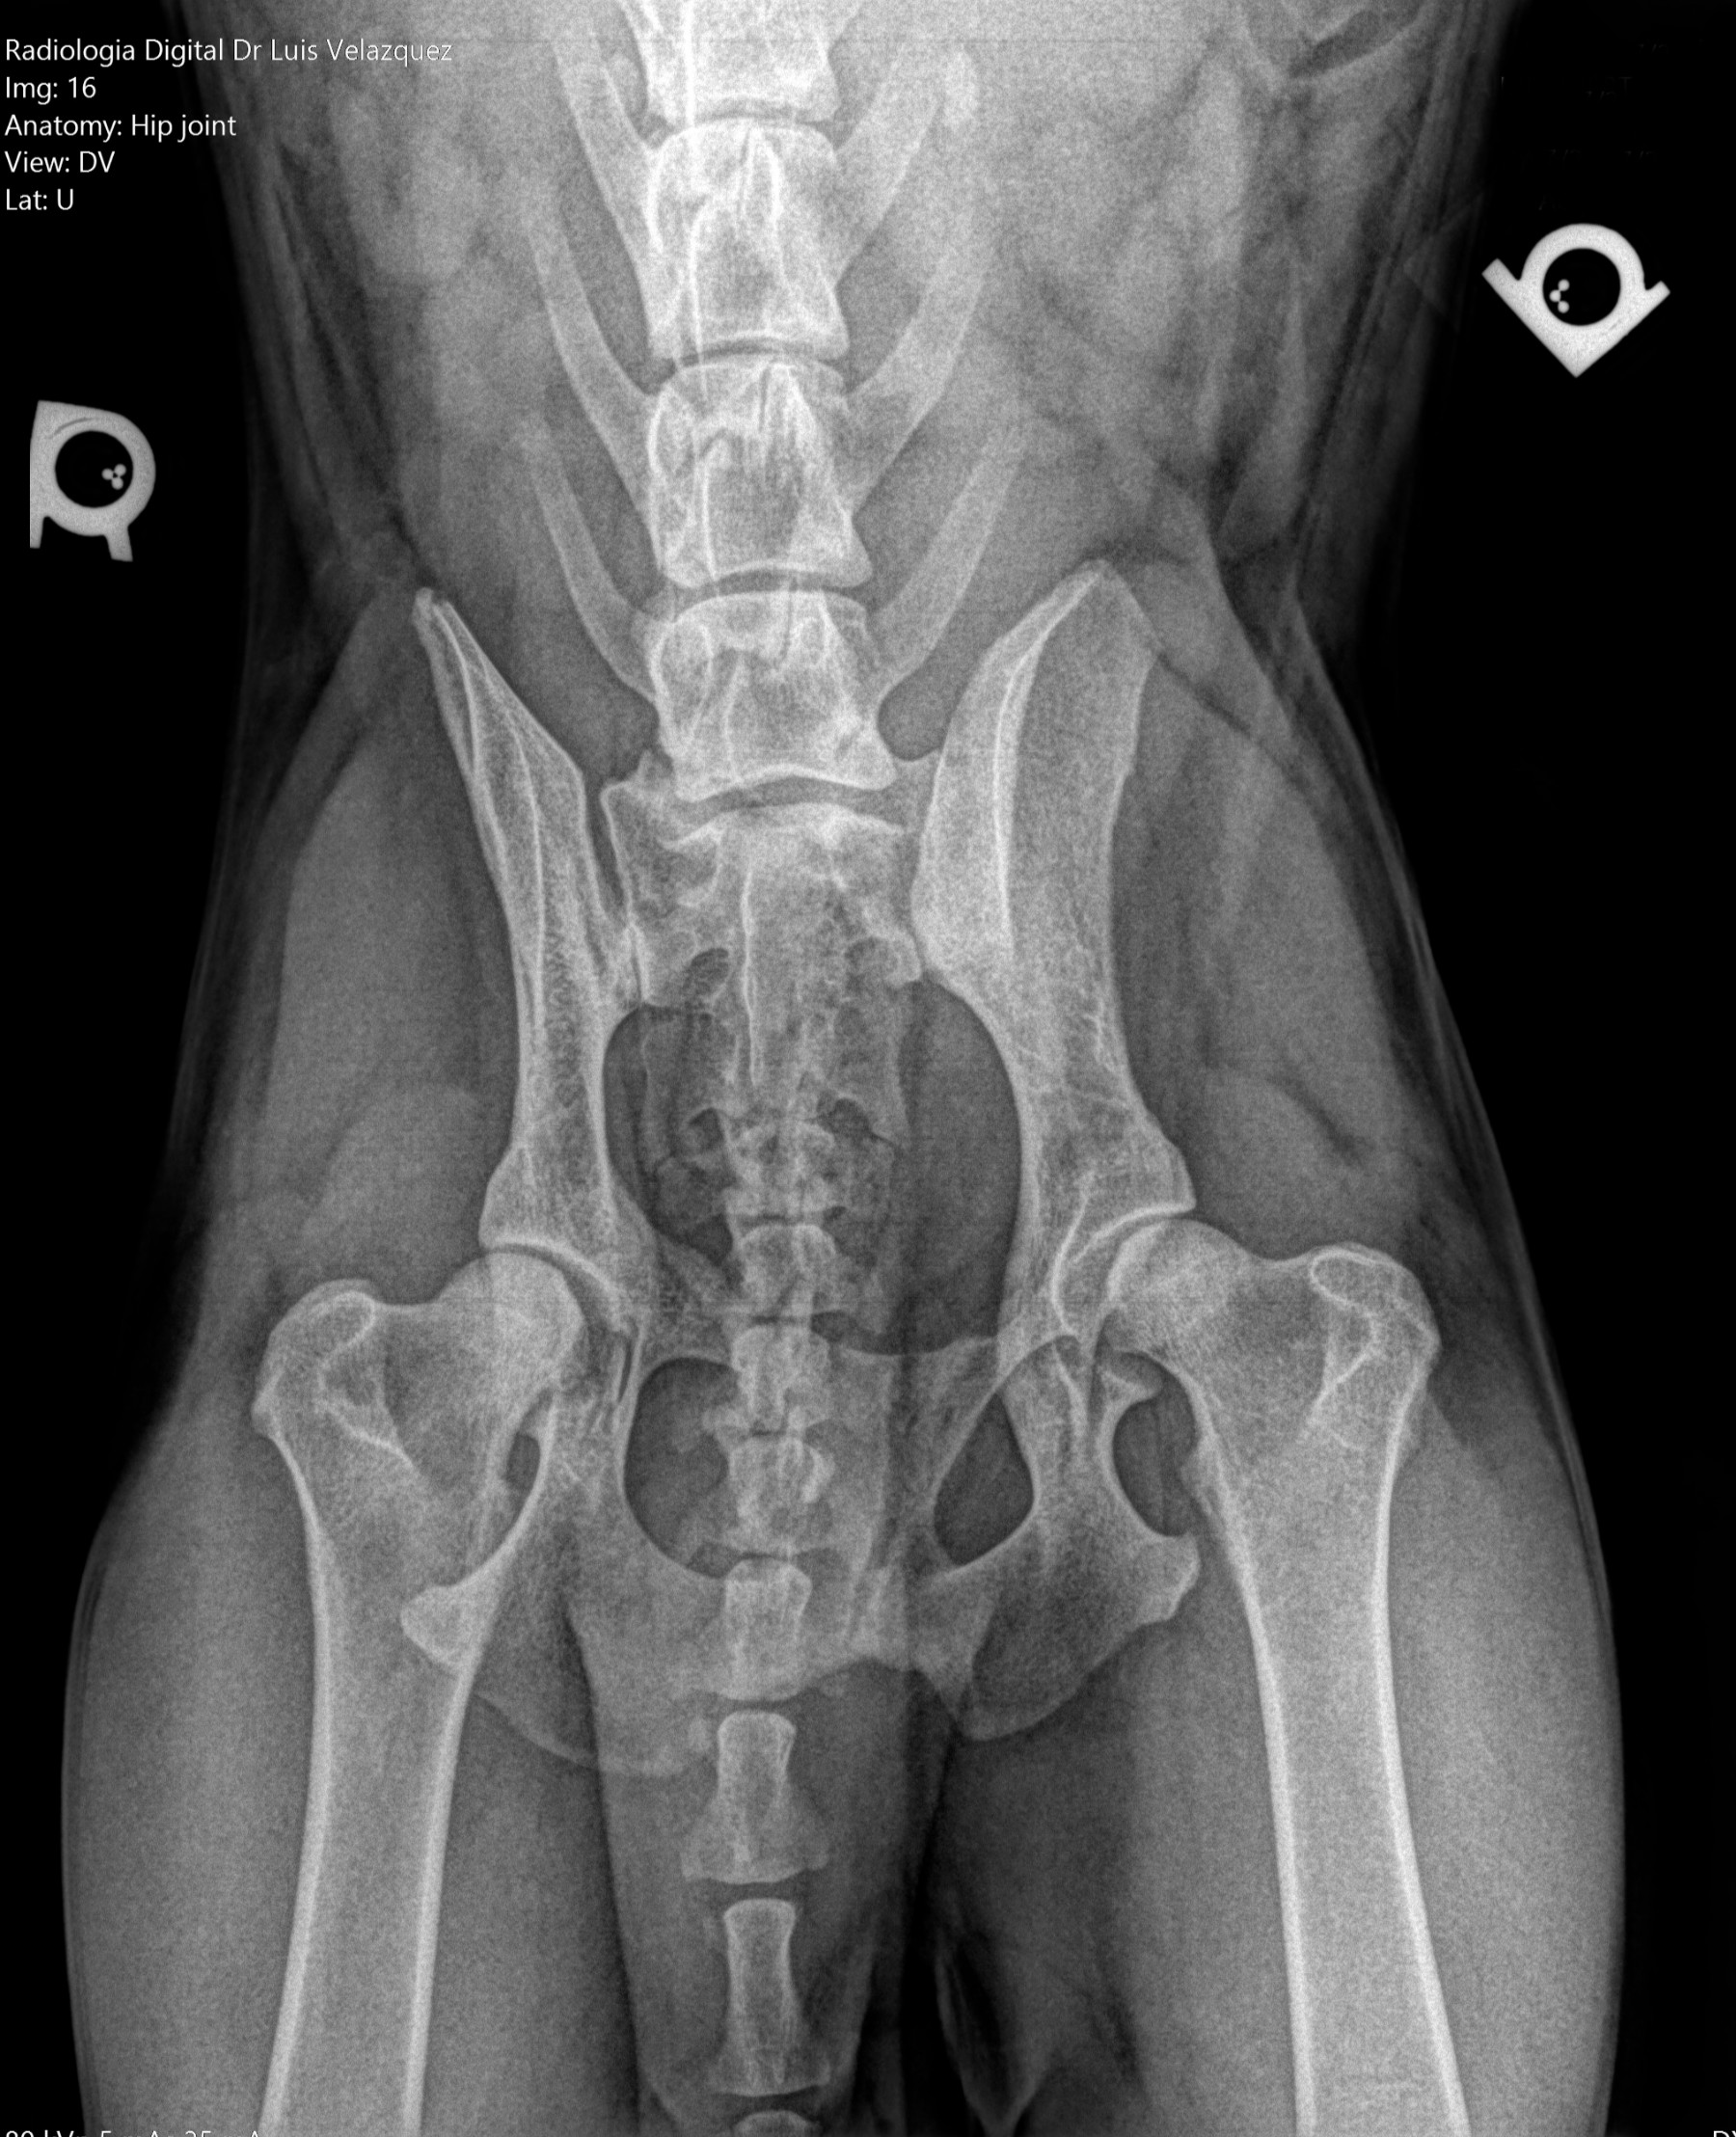

Radiología Digital como Herramienta Complementaria en el Dictamen de Bienes Muebles

Desde el descubrimiento de los rayos “X” y las placas radiográficas por Wilhelm Conrad Roentgen y su posterior difusión a través de la Asociación Físico médica de Wurzburg el 28 de diciembre de 1895, que fue la primera asociación que habló de los nuevos rayos que podían penetrar el cuerpo y fotografiar los huesos, ha habido muchos cambios tanto en la forma de obtener, procesar e incluso en la forma de visualizar, manejar y almacenar las placas radiográficas.